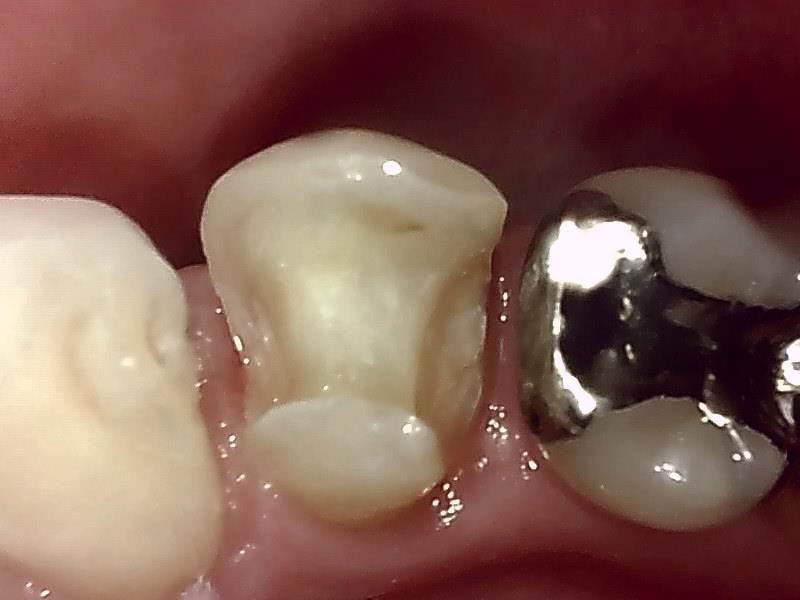

セラミックインレーの装着前の窩洞形成(写真)

仮歯の装着して近心歯肉の回復を待つ。

仮歯の装着後、歯肉の治癒期間は後1~2週間後程度になる。